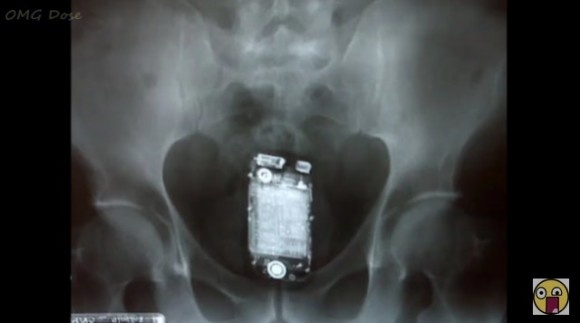

アメリカの米国消費者製品安全員会の緊急治療室への訪問者データベースによると、純粋な事故以外にも体内に実に様々なモノを自ら押し込んでしまった人が、取り出せなくなって病院に駆けつけているのがわかる。

去年1年間で、アメリカ人が耳や鼻、そして秘密の穴に入ってしまった、もしくは入れてしまったものは多岐にわたるが、ダントツの異物は大人の世界にのみ存在するおもちゃだという。

女性よりも男性に多い層で、男性の飽くなき好奇心が「むちゃしやがって...」な状況を作り上げてしまったようだ。

ということで、いったいどんなモノがアメリカ人の体内に入っていたのか、早速その一例を見てみよう。